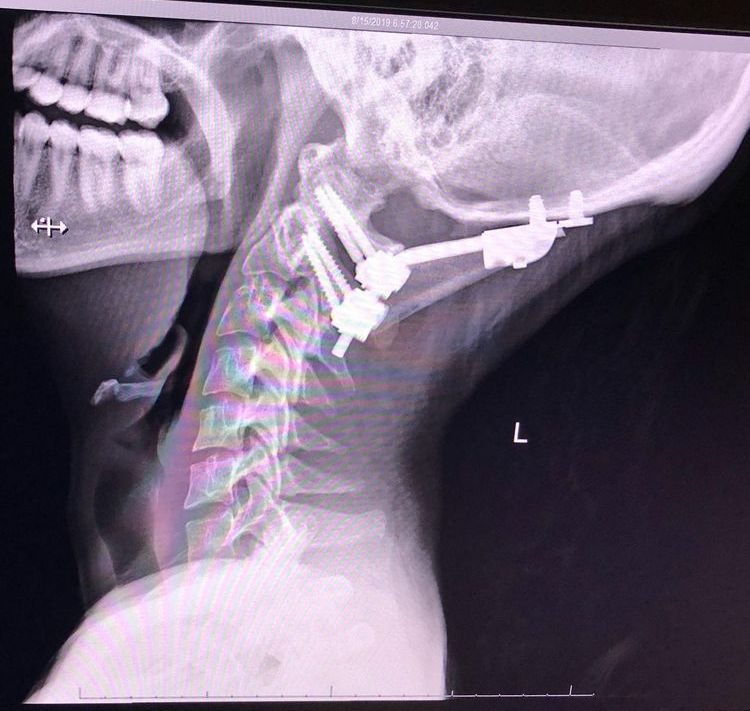

Медицинское приспособление для поддержания шеи в правильном положении при заболевании соединительной ткани, которое называется синдром Элерса-Данлоса

«Связки, удерживающие мою голову, больше не хотели выполнять свою работу, и моя шея ослабла».